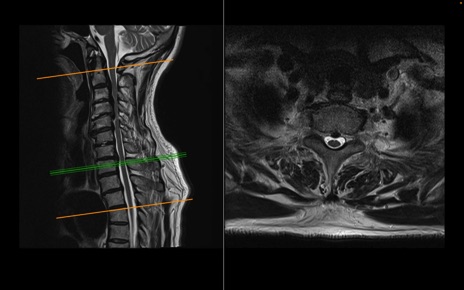

頚椎MRI

T2WI(横断像)

T2WI(矢状断像)